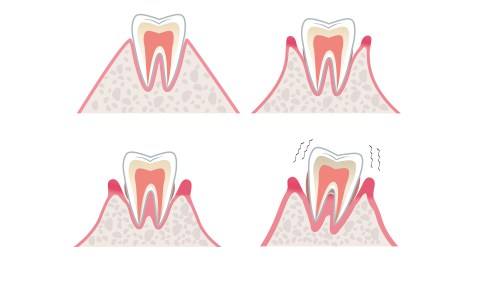

我们的牙齿是靠着牙根周围丰富的软组织和骨组织包围支撑才能牢固稳定地在口腔之内。当包围着牙根的组织出现了问题的时候,就会降低对牙根的包裹能力导致牙齿的松动。牙周组织的改变主要有下面这么几类:

1、很多成年人都患有慢性牙周炎,他们并不注意,直到牙槽骨慢性吸收到一定程度时,就会出现牙齿松动的现象。 2、有一些人晚上睡觉时大力磨牙或者紧咬牙齿,长时间保持这样的习惯,也会造成牙齿松动。 3、牙周膜组织的急性炎症水肿也会造成牙齿咬合疼痛和牙齿松动的问题。 4、糖尿病等疾病的并发症。

牙齿的松动在临床上由轻到重分为I、II、III度。